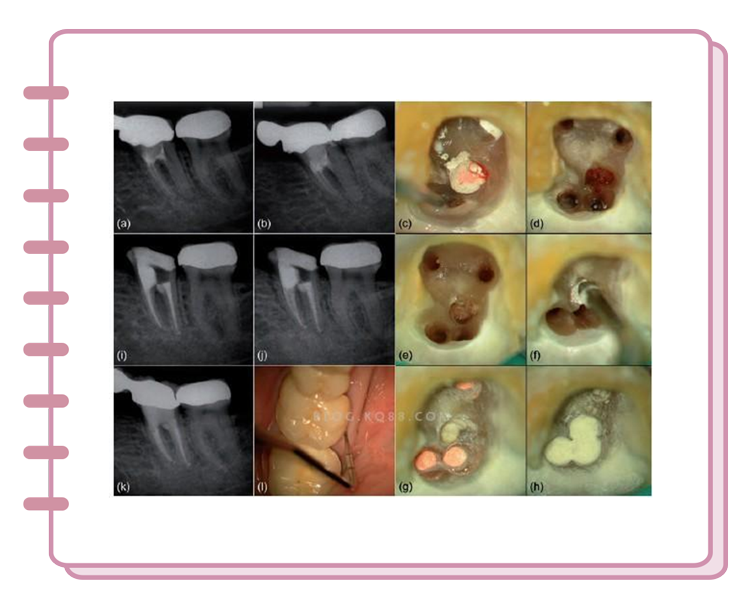

当牙神经暴露

只能采用根管治疗(俗称杀神经)

把原本的牙神经全部杀死后

再用人造根管和牙冠代替